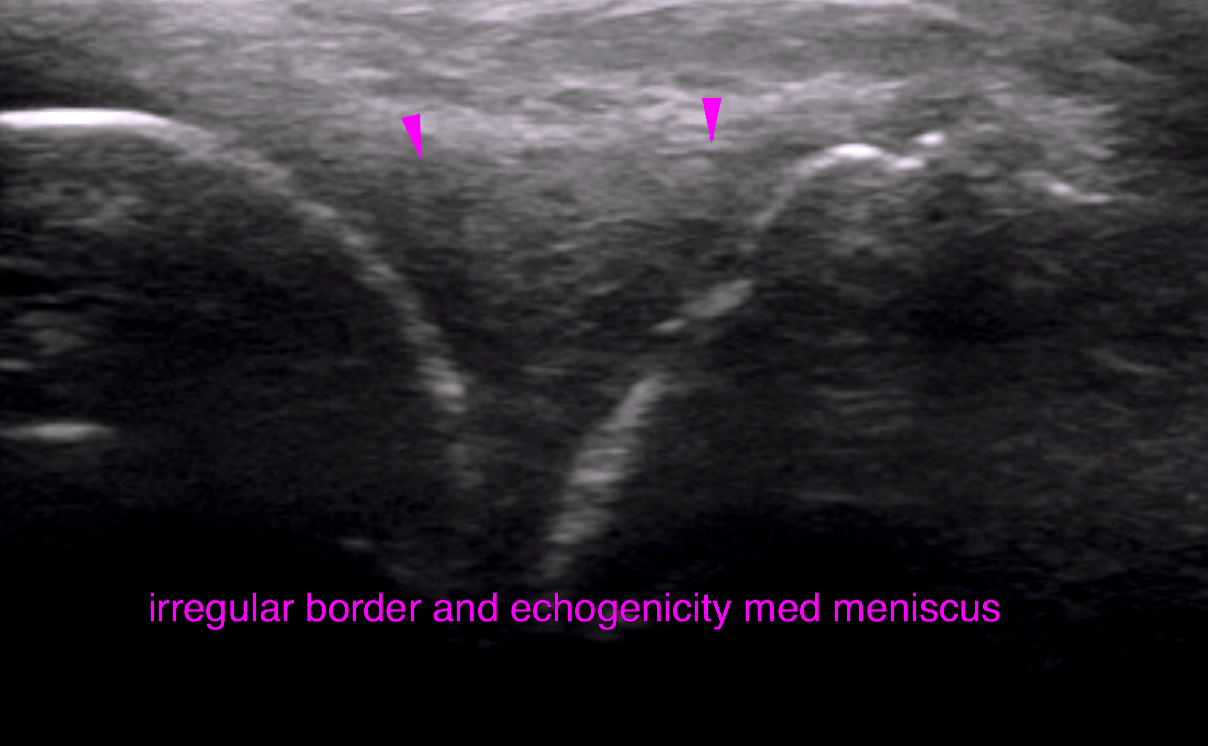

This 6 year old MN Belgian Shepherd dog has a history of intermittent lameness of over 1 year duration. Worsens with exercise. Decreased muscle mass right hind. Positive cranial drawer sign and CTT, moderate medial buttress sign.

Evaluate right stifle prior to TTA stabilization